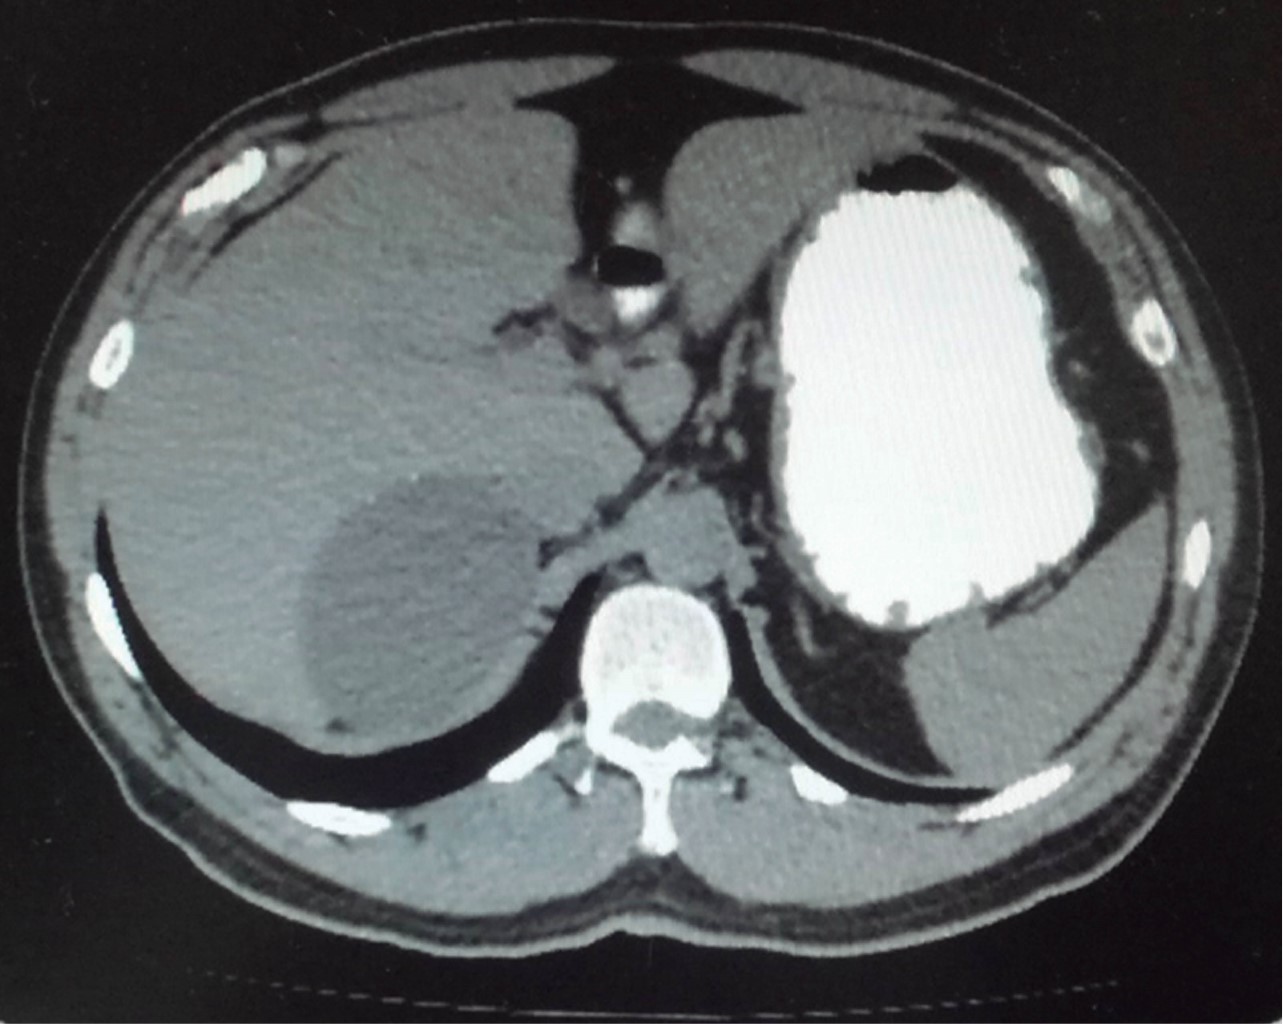

Biometría hemática, pruebas de función hepática, renales, TP y TPT de mayo de 2018 normales. No se realiza cortisol, aldosterona, catecolaminas urinarias ni metanefrinas. Tomografía de mayo reporta en glándula suprarrenal derecha imagen hipodensa con diámetros máximos de 101 mm, calcificaciones en su interior con efecto ocupativo y compresivo sobre las estructuras vecinas (Figuras 3, 4, 5 y 6). Completándose su valoración preoperatoria por medicina interna, se programa abordaje quirúrgico anterior abierto y bajo profilaxis antibiótica con ceftriaxona 2 g en dosis única, se realiza incisión subcostal derecha, destechamiento con electrocauterio de quiste suprarrenal derecho de 10 × 9 cm, con adherencias al hígado, contenido de aproximadamente 400 ml de líquido hialino y calcificaciones de alrededor de 20 × 40 mm en su interior. Se coloca drenaje abierto, penrose de ½" (19 mm) en espacio subfrénico ante la sospecha de hemorragia postoperatoria.

Figura 3

Figura 4